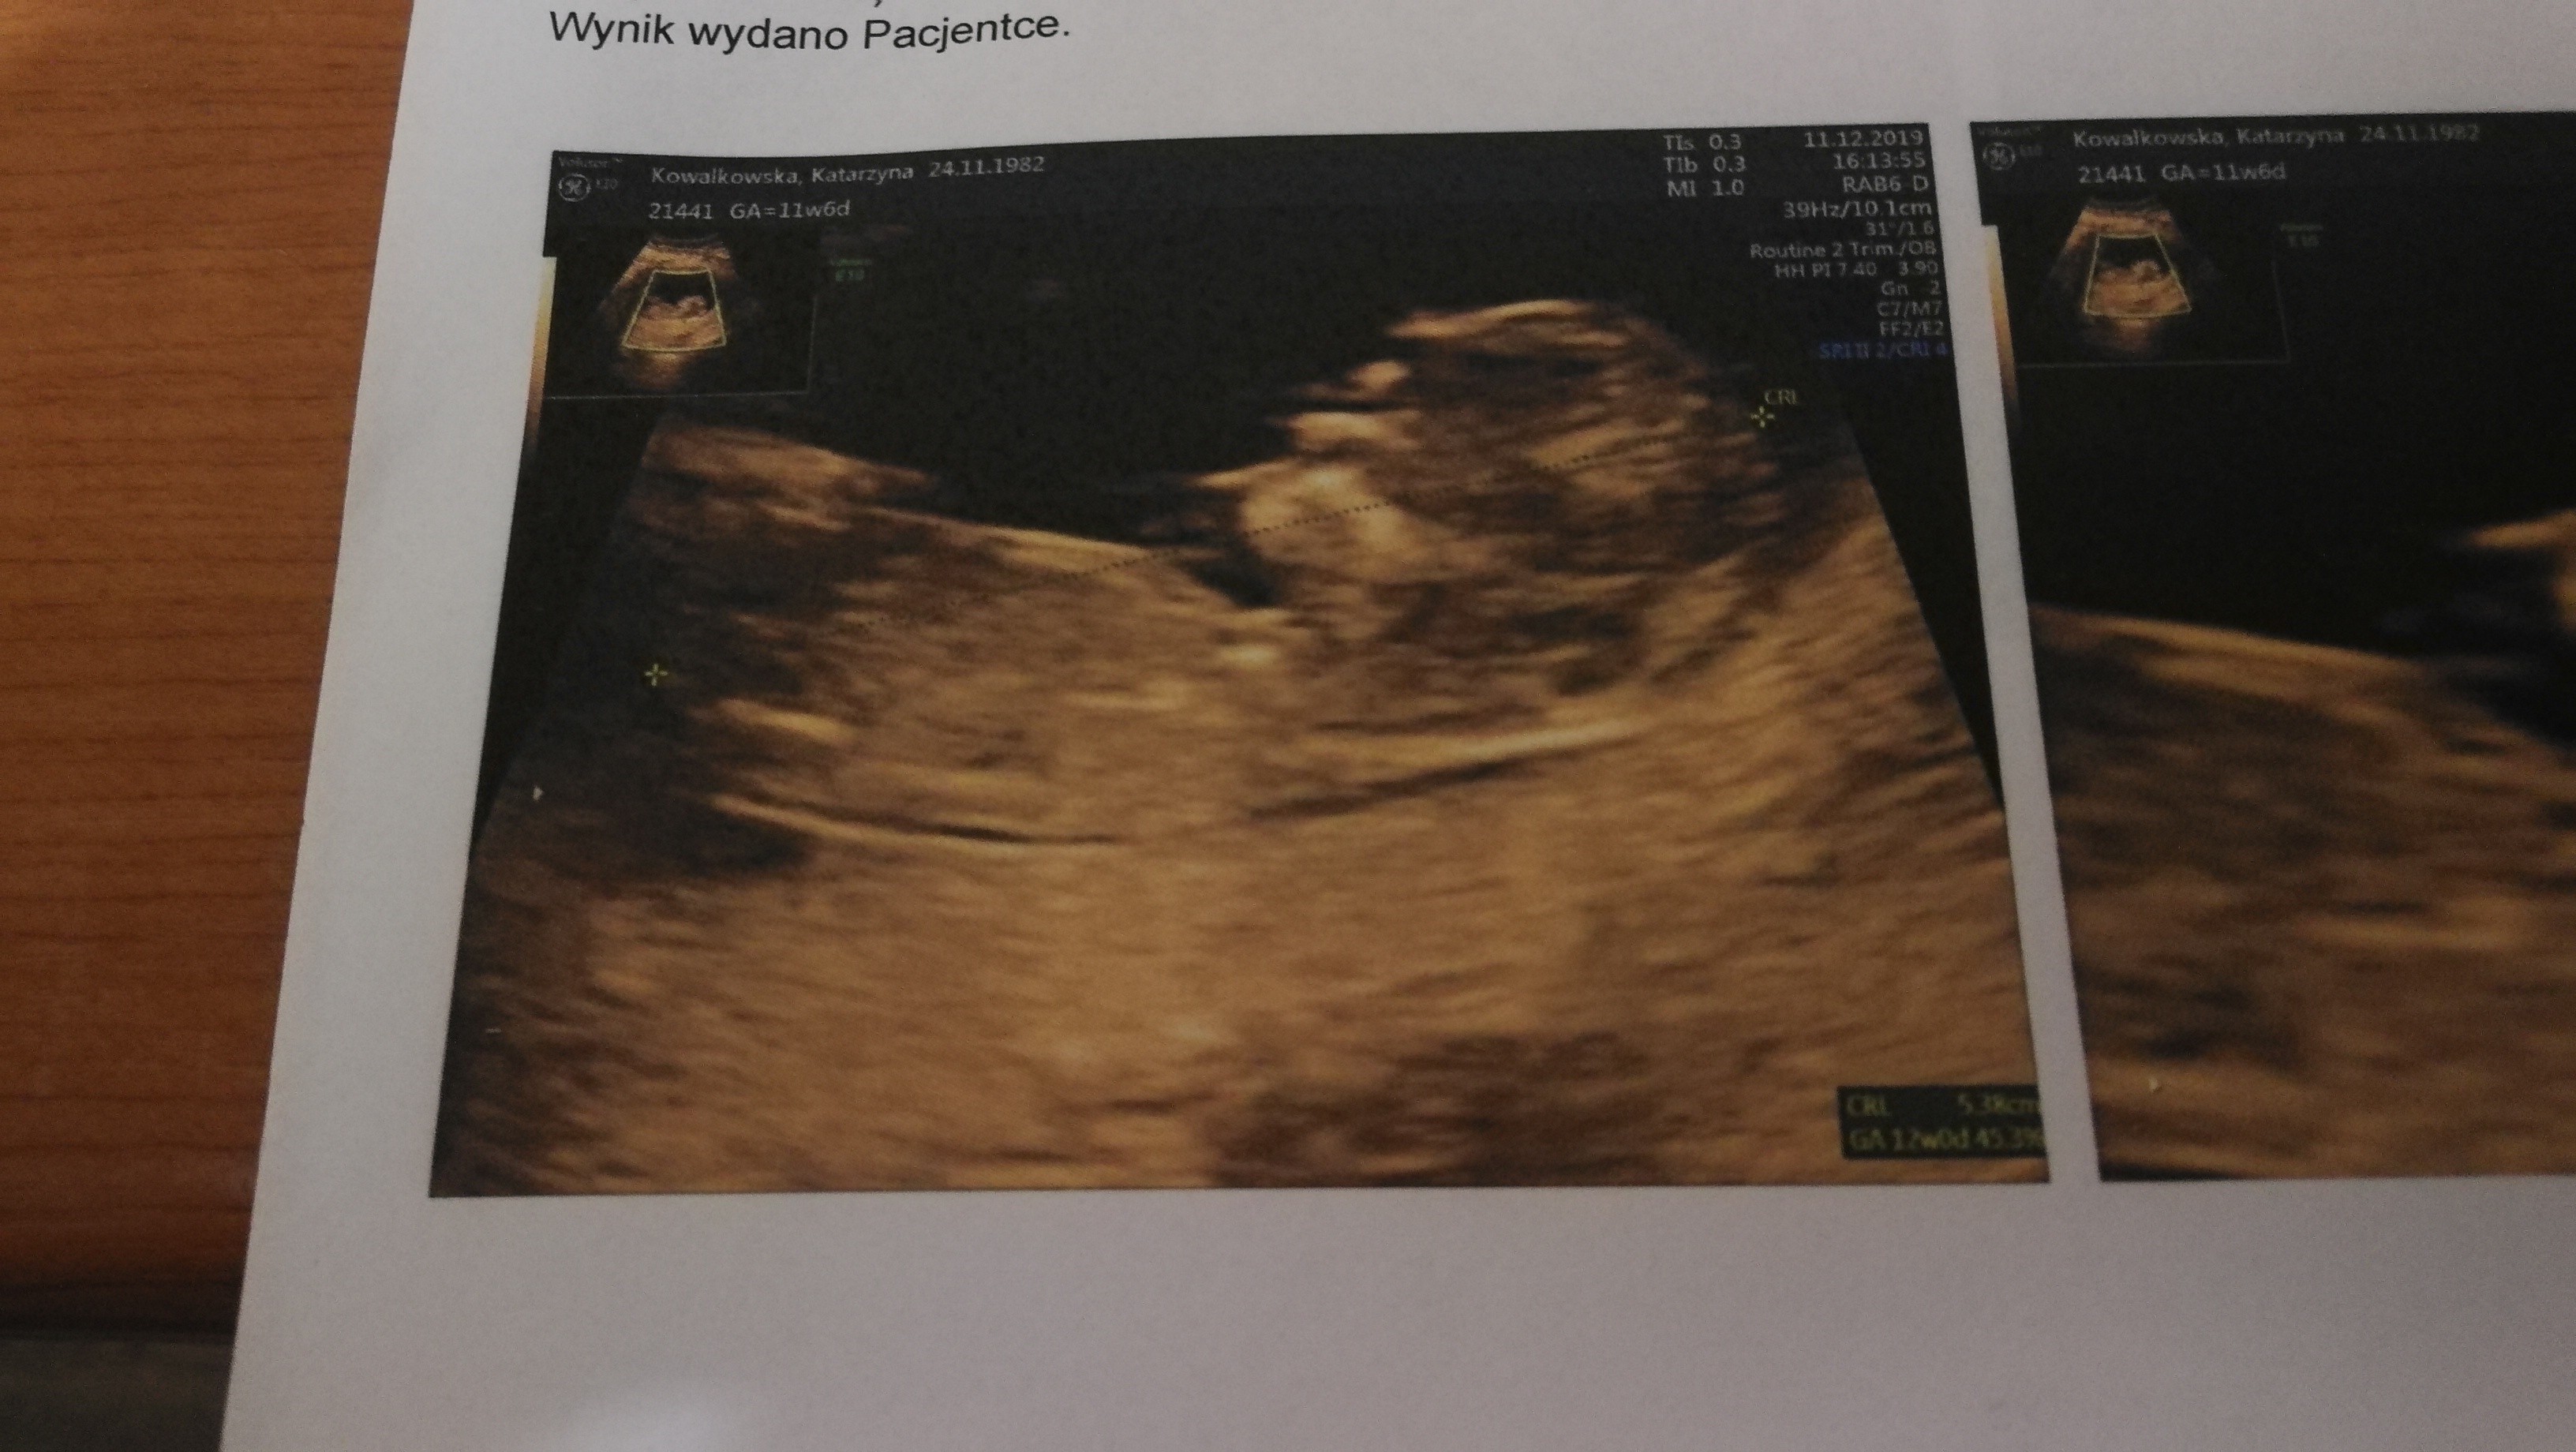

Jestem po badaniach prenetalnych wszystko ok z dzidziusiem. Co do plamien to mam nisko łożysko i mam nakaz nic nie robic i nie dźwigać.

Ale słyszałam serduszko i tak ładnie bylo go widać taki maluszek. 5.38 cm 😊

• IMG_20191211_175501.jpg

IMG_20191211_175501.jpg

927,6 KB · Wyświetleń: 133